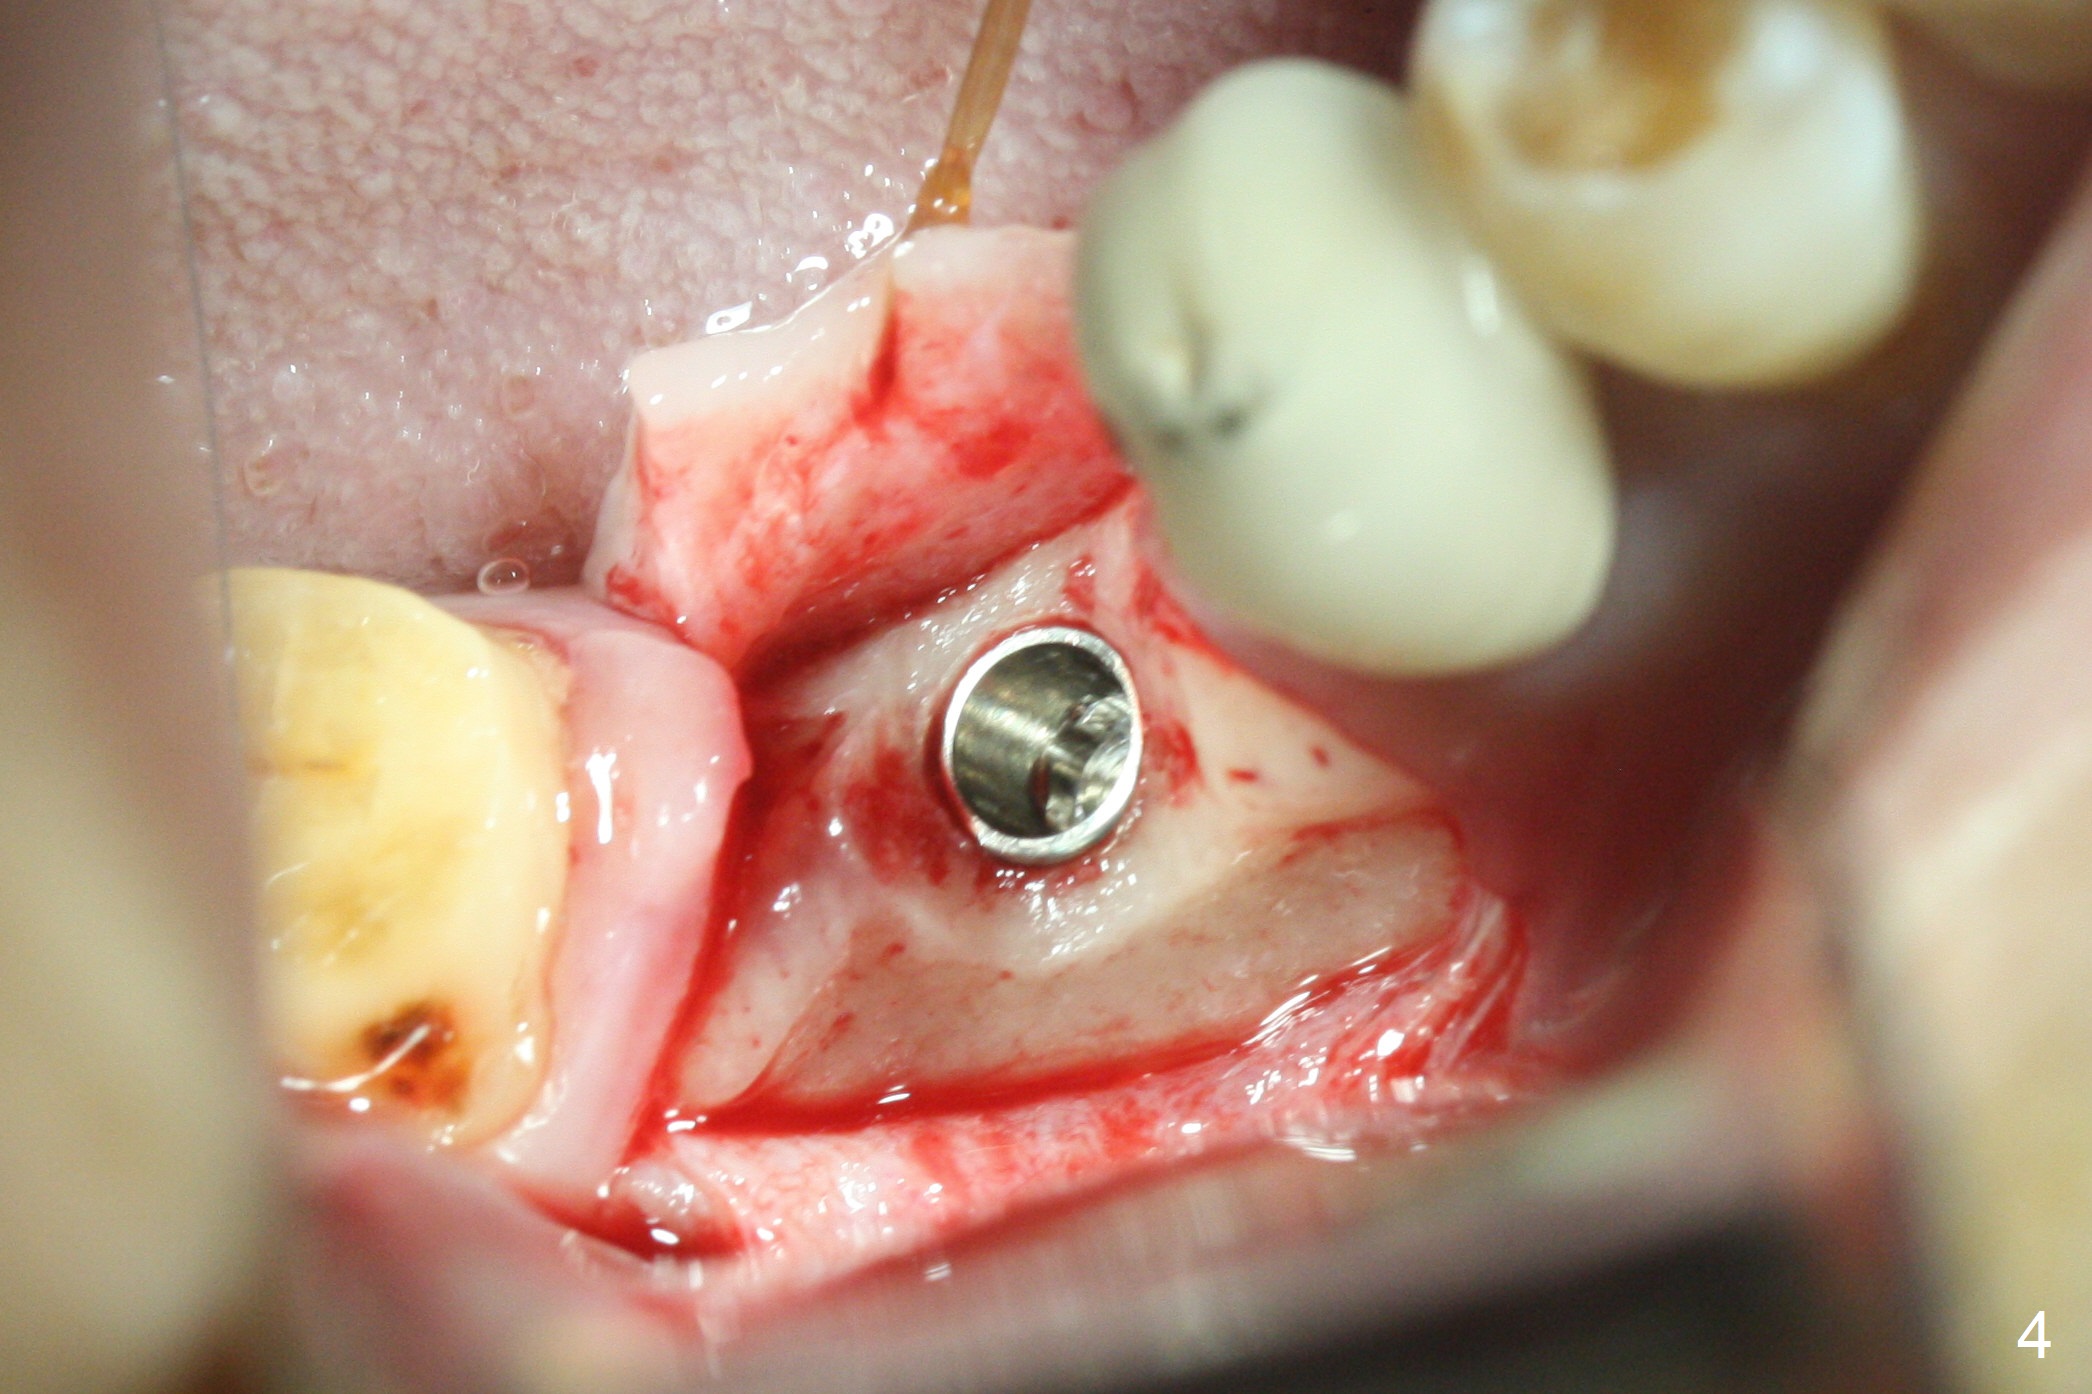

The apparently narrow ridge at #30 before bridge sectioning (Fig.1) is confirmed with incision (Fig.2). Following ridge reduction, osteotomy is initiated with 2 mm pilot drill (Fig.3). When a 3.8x12 mm SM narrow implant is placed with 40 Ncm, there is 1-2 mm cortical bone buccolingually (Fig.4,5). The thick cortices do not seem to be easy to be bent, i.e., expanded. RCT is finished at #31 one month post implant placement (Fig.6,7), the flattened ridge appears to have started to undergo remodeling. Ridge reduction makes it possible for the implant to remain subcrestal postop (Fig.4). The bone surrounding the implant may reduce the likelihood of implant fracture. The crowns at #30 and 31will be fabricated together with light occlusion at #30. In fact the splinted provisional dislodges. There appears dense bone formation 3 months postop (Fig.8 *). The drawback of using a SM narrow implant is that a narrow abutment has to be used (4.8x4(4.5) mm). The implant crown is dislodged immediately after the patient finishes lunch. Following recementation, the occlusion is reduced. In fact, UF or IBS has no such drawback: the implant could be small, but the abutment could be large. One year post cementation, the crown at #31 needs recementation (Fig.9); the bone density next to the coronal implant increases (*).